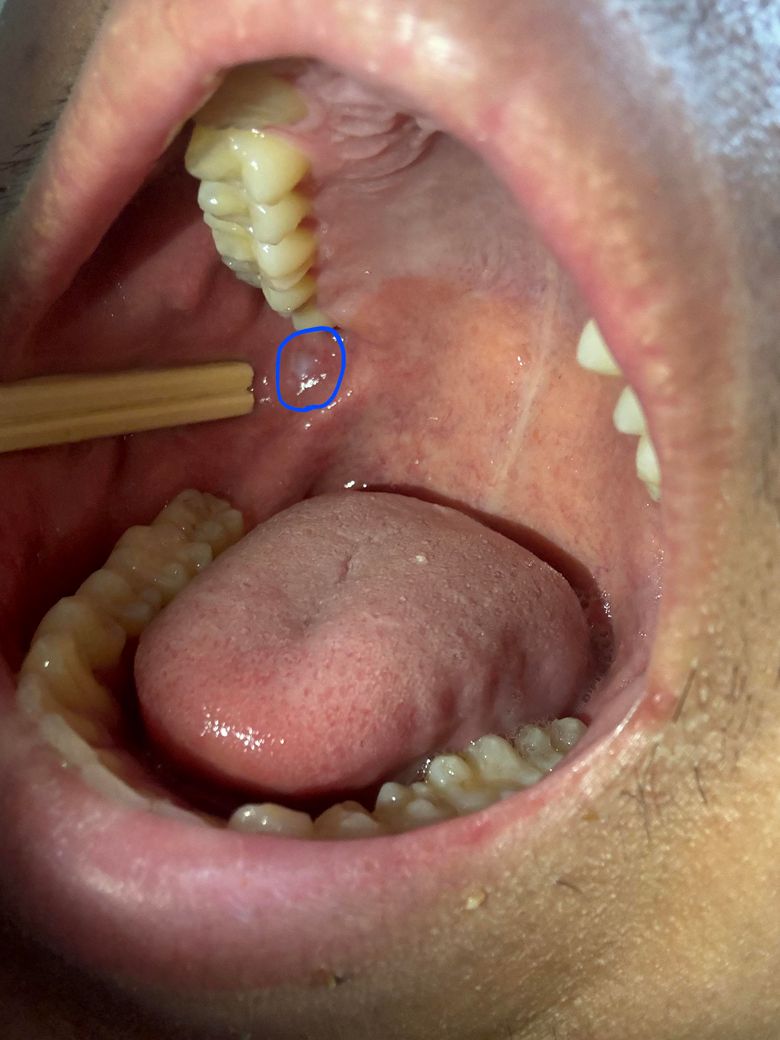

사진속 동그라미친부분이 어저께 갑자기 하얀색으로 변한걸 확인했습니다. 걱정되는게 저게 백반증처럼 위험한건가 싶어서 여쭙습니다. 실제 거울로보면 사진보다 20%더크게, 더 선명하게 하얗게 보이는데 저부분이 또 사랑니에 자극받는 자리라서요.. 물론 사랑니가 점막을 계속 상처입혔지만 그보다 더 심했던 반대편위치는 멀쩡합니다. 정말 위험한걸까요?

• 현재 사진으로는 정확한 판단이 어렵지만 사진상으로 보아서는 사랑니가 지속적으로 해당 부위를 자극하여 나타난 것으로 보여집니다. 특별히 모양상 문제는 없으나 해당 연조직이 2주 이상 지속되거나 통증 및 불편감 양상이 달라진다면 반드시 치과 방문 후 감별진단을 해야 합니다.

• 사진상 단순 구내염으로 보이며 사랑니가 해당 부위를 자극시키면 더 커질 수도 있습니다.

• 반대쪽 사랑 내가 잇몸을 자극하게 되면 하얀색으로 보일 수 있습니다. 이런 증상은 대부분 자극이 줄어들게 되면 없어지는 경우가 많습니다. 사랑니로 인해서 반대쪽 잇몸에 상처가 생긴다면 사랑니를 발치해주는 것이 좋을 수 있습니다.